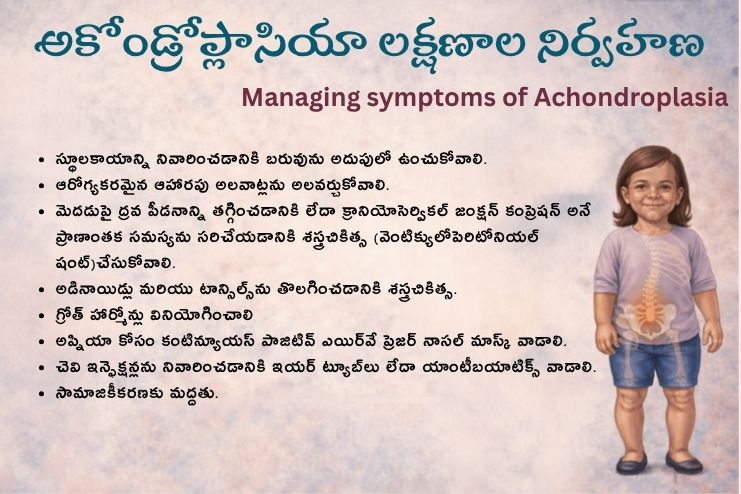

అకోండ్రోప్లాసియా లక్షణాల నిర్వహణ ఎలా? Managing symptoms of achondroplasia

అకోండ్రోప్లాసియా నిర్వహణ అనేది సంభావ్య సమస్యల పట్ల శ్రద్ధ వహించడంపై దృష్టి పెడుతుంది. వాటిలో ఇవి ఉండవచ్చు:

- స్థూలకాయాన్ని నివారించడానికి బరువును అదుపులో ఉంచుకోవడం మరియు ఆరోగ్యకరమైన ఆహారపు అలవాట్లను ప్రోత్సహించడం.

- మీ మెదడుపై ద్రవ పీడనాన్ని తగ్గించడానికి లేదా క్రానియోసెర్వికల్ జంక్షన్ కంప్రెషన్ అనే ప్రాణాంతక సమస్యను సరిచేయడానికి శస్త్రచికిత్స (వెంటిక్యులోపెరిటోనియల్ షంట్).

- అడినాయిడ్లు మరియు టాన్సిల్స్ను తొలగించడానికి శస్త్రచికిత్స.

- గ్రోత్ హార్మోన్లు.

- అప్నియా కోసం కంటిన్యూయస్ పాజిటివ్ ఎయిర్వే ప్రెజర్ (CPAP) నాసల్ మాస్క్ వాడకం.

- చెవి ఇన్ఫెక్షన్లను నివారించడానికి ఇయర్ ట్యూబ్లు లేదా యాంటీబయాటిక్స్.

- సామాజికీకరణకు మద్దత